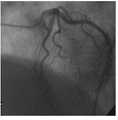

X射线冠状动脉造影(coronary angiography,CAG)是目前临床普遍采用的诊断冠心病的介入影像技术。将特制的导管,经皮穿刺从股动脉或上臂的桡动脉逆行插入,送至升主动脉,在X射线透视图像的指导下,探寻左或右冠状动脉口插入,然后注入造影剂,使冠状动脉显影,利用造影机从不同角度进行电影摄影或快速连续摄片。 Coronary angiography (CAG) is an interventional imaging technique commonly used clinically to diagnose coronary heart disease. A special catheter is retrogradely inserted from the femoral artery or the radial artery of the upper arm through percutaneous puncture, and sent to the ascending aorta. Under the guidance of the X-ray fluoroscopy image, it is inserted into the left or right coronary artery, and then the contrast agent is injected to make the coronary Arterial imaging, using a contrast machine to perform cinematography or filming in rapid succession from different angles. the

图3 是采用本发明的对一帧CAG图像进行分割和血管骨架提取的实施例图像;其中,图3(a)是原始的造影图像;图3(b)是自适应阈值分割的结果;图3(c)是区域生长的结果;图3(d)是血管骨架提取的结果;Fig. 3 is the embodiment image that adopts the present invention to carry out segmentation and vascular skeleton extraction to a frame of CAG image; Wherein, Fig. 3 (a) is original angiography image; Fig. 3 (b) is the result of adaptive threshold segmentation; Fig. 3(c) is the result of region growing; Figure 3(d) is the result of vessel skeleton extraction;

附图3和4是对PHILIPS Integris CV全数字血管造影机临床采集到的左冠造影图像序列的实验结果。采集速率为15帧/秒、图像大小为512×512(像素)、灰阶为256、像素尺寸为0.3mm,图像序列的拍摄角度分别为LAO46° CRAN21°和RAO30°CAUD24°。附图3是对一帧CAG图像进行分割和血管骨架提取的结果。附图4是对一对CAG图像进行弹性配准的结果。 Figures 3 and 4 are the experimental results of the left coronary angiography image sequence collected clinically by the PHILIPS Integris CV full digital angiography machine. The acquisition rate is 15 frames per second, the image size is 512×512 (pixels), the gray scale is 256, and the pixel size is 0.3mm. The shooting angles of the image sequences are LAO46°CRAN21°and RAO30°CAUD24°. Figure 3 is the result of segmenting a frame of CAG image and extracting vessel skeleton. Figure 4 is the result of elastic registration of a pair of CAG images. the